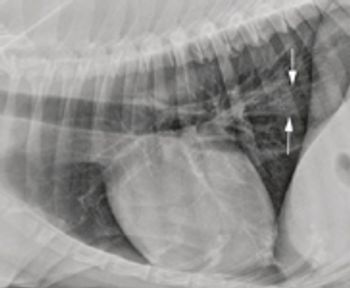

Megaesophagus is a condition in which the esophagus has reduced peristalsis, and has poor tone at rest. The esophagus can have a mild, focal motility problem, or the entire organ may be dilated and functioning poorly.